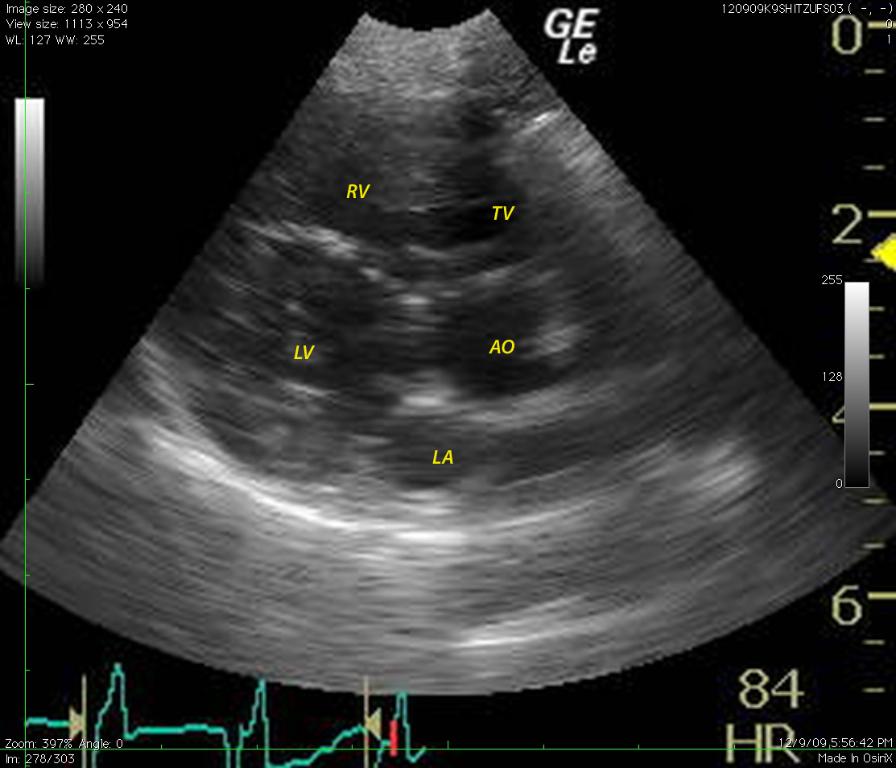

A 6-year-old FS Shih Tzu presented for exercise intolerance and cyanosis under stress. The clinical exam was otherwise unremarkable. A slight right and left sided murmur was auscultated. Right sided cardiomegaly was noted on radiographs. Radiographs (Image 1): generalized right sided cardiomegaly is noted. There is no evidence of pulmonary congestion. The lung pattern is unremarkable.